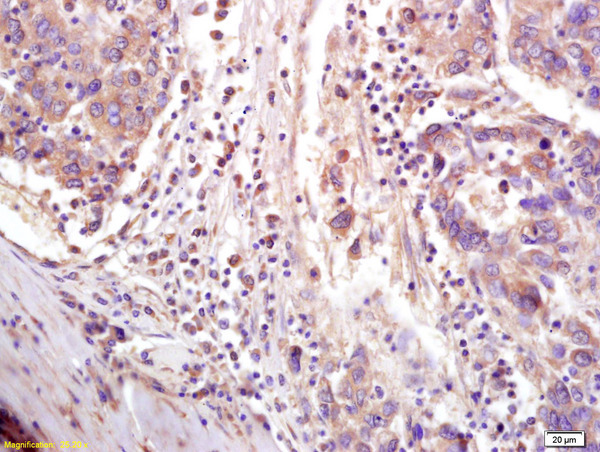

- Main image

- Experimental details

- Formalin-fixed and paraffin embedded human lung carcinoma labeled with Anti-CTCF Polyclonal Antibody, Unconjugated (bs-3778R) at 1:200 followed by conjugation to the secondary antibody and DAB staining.

- Sample type

- Human

- Other comments

- Lung